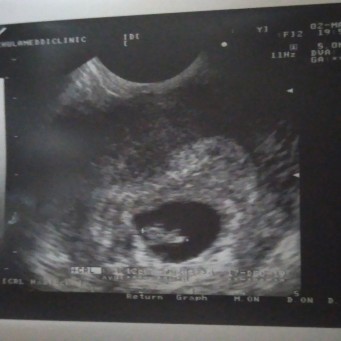

ภาวะแท้งคุกคาม

จากที่เลือดออก ไปหาหมอที่คลินิคมาแล้วนะค่ะหมอบอกน้องยังอยู่ตอนนี้ได้7w2d น้องหัวใจเต้นแล้ว ดีใจที่เค้ายังอยู่แข็งแรง